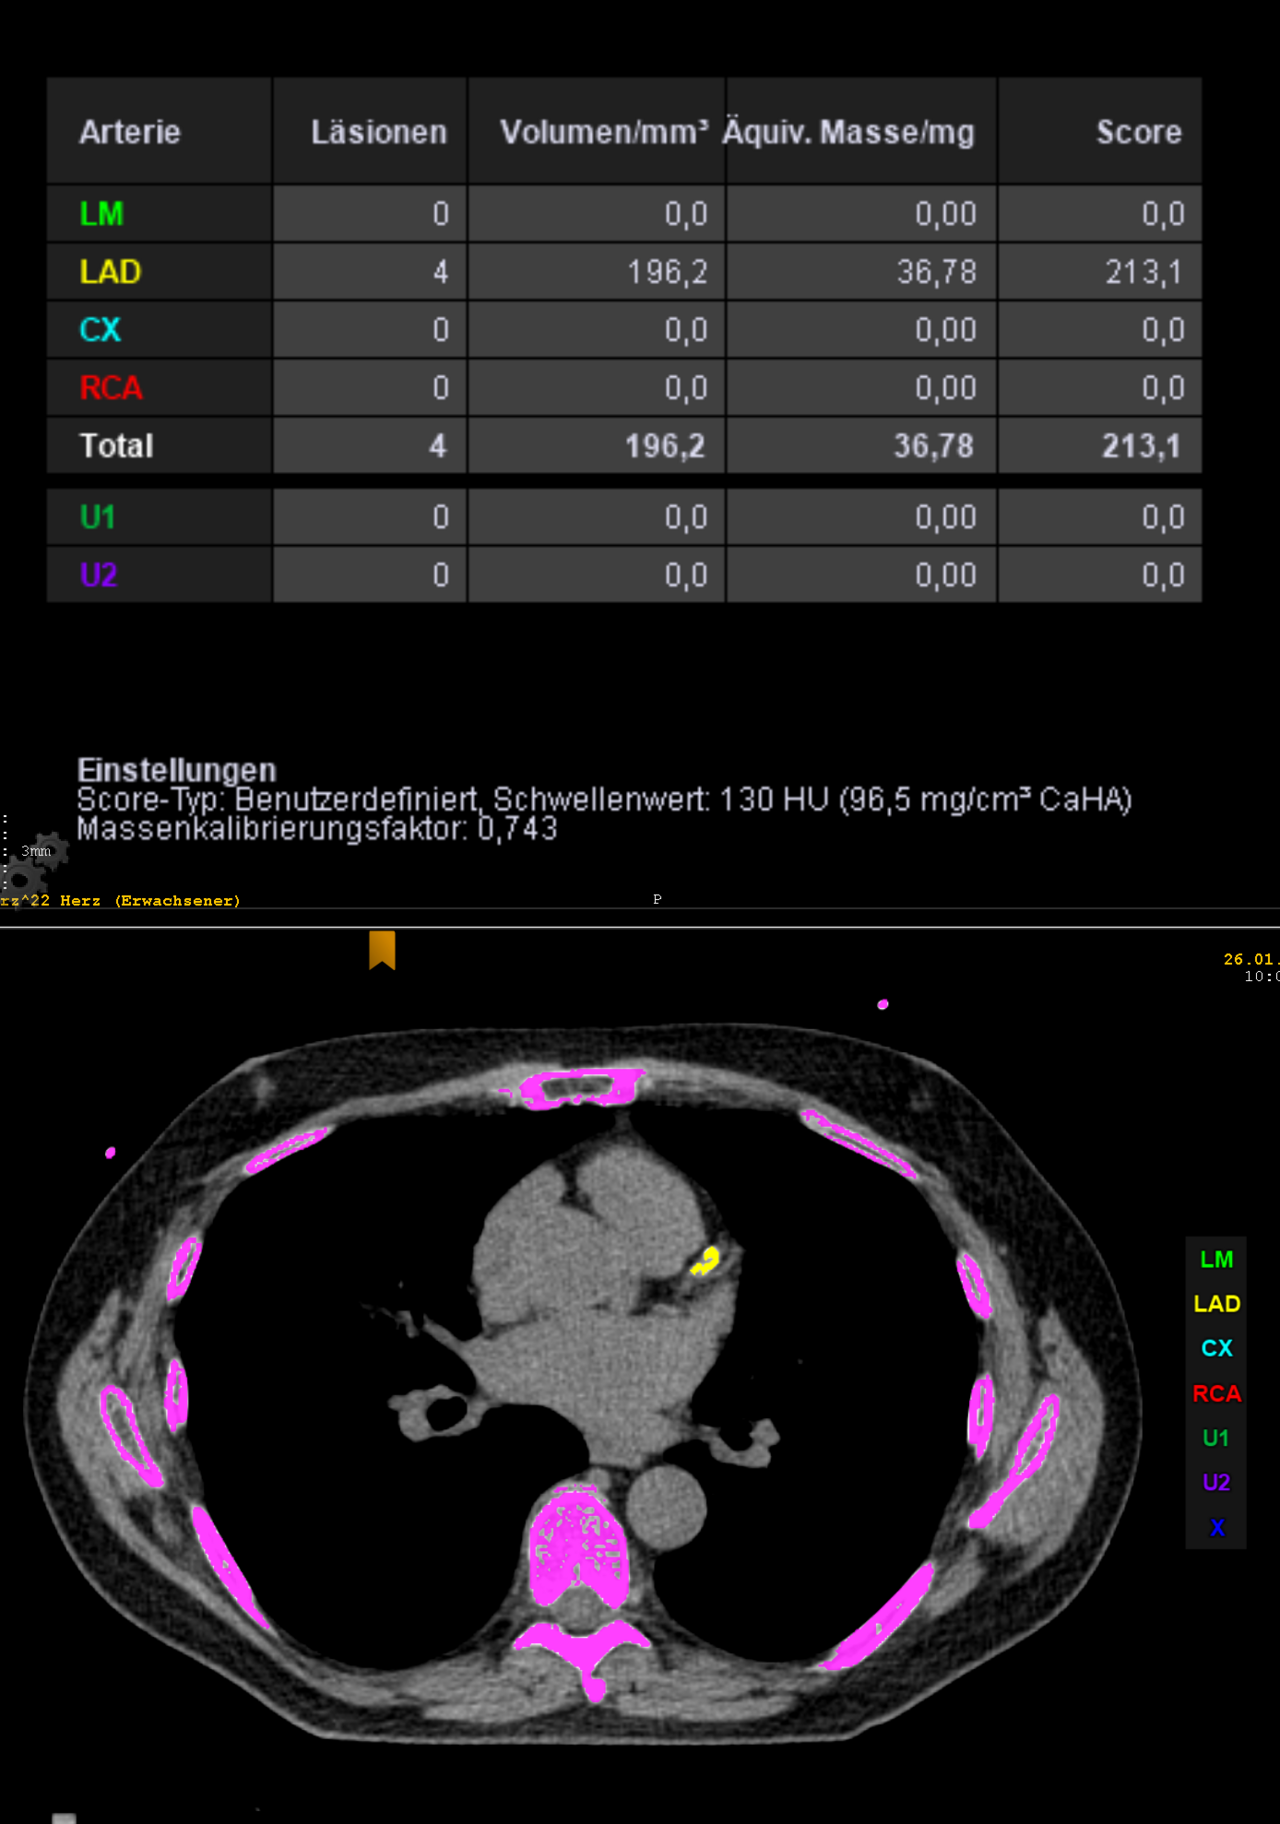

CCTA — Agatston Calcium Score

CT coronary calcium scoring (Agatston score) showing calcified coronary plaques

CT Downloaded 2026-03-15

Ct

Calcium Score 120 kVp

Wikimedia Commons: CCTA Agatston-Score.png